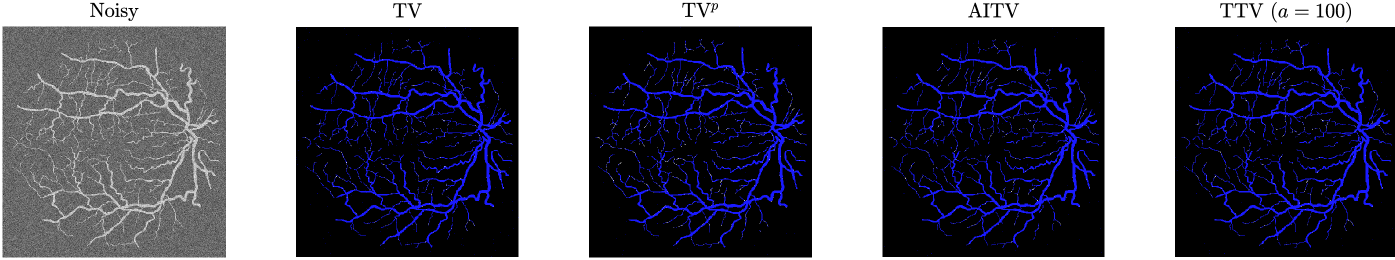

Refer to caption

(a) Vessel 1

(b) Vessel 2

Figure 2: Segmentation results of Figures 1(a)-1(b) (after normalization) corrupted by Gaussian noise of mean 0 and variance 0.01.

Before applying the segmentation algorithms, the images in Figure 1 are normalized to [0,1]01[0,1][ 0 , 1 ] followed by Gaussian noise corruption. The retina vessel images are corrupted with Gaussian noise of mean 0 and variance 0.01. Table I reports the performances and times of the segmentation methods on the retina vessel images while Figure 2 shows some of their results. TTV (a=10,100)𝑎10100(a=10,100)( italic_a = 10 , 100 ) has the highest DICE and Jaccard similarity indices across the three images although requiring about 80 seconds to complete, thereby being slower than TV and TVp. The brain images are corrupted with Gaussian noise of mean 0 and variance 0.04. Table II reports the performances and times of the multiphase segmentation, while Figure 3 shows the segmentation results of Figure 1(g). By its DICE and Jaccard similarity indices, TTV (a=1)𝑎1(a=1)( italic_a = 1 ) is best at segmenting CSF across the four images while TTV (a=5,10)𝑎510(a=5,10)( italic_a = 5 , 10 ) remains competitive against AITV in segmenting GM and WM. On average, TTV (a=1,5)𝑎15(a=1,5)( italic_a = 1 , 5 ) is among the top two best-performing methods. Although it can be outperformed by AITV, it is at least three times faster. In Figure 3, we see that TTV (a=5)𝑎5(a=5)( italic_a = 5 ) is most effective in segmenting CSF, especially compared to TV and TVp. Moreover, comparable to TV and AITV, it is able to identify most of the GM and WM regions. Overall, using TTV, the proposed method is able to effectively identify narrow, thin regions such as the retina vessels and CSF.